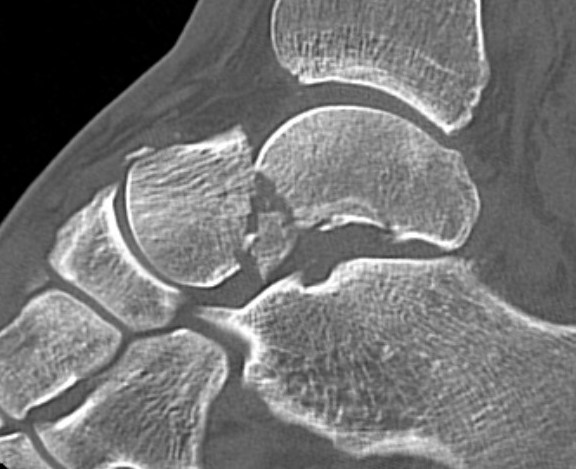

Canale view

- evaluates talar neck

- foot everted 15 deg

- look for medial shortening / varus

Xrays

| AP | Lateral | Canale View |

|---|---|---|

| Entry point of the screws |

Evaluate neck reduction

|

Evaluates the neck reduction |

Lateral off articular surface Medial through articular cartilage |

Depth of screws |

Beam angled 75o to foot Foot 15o pronated |